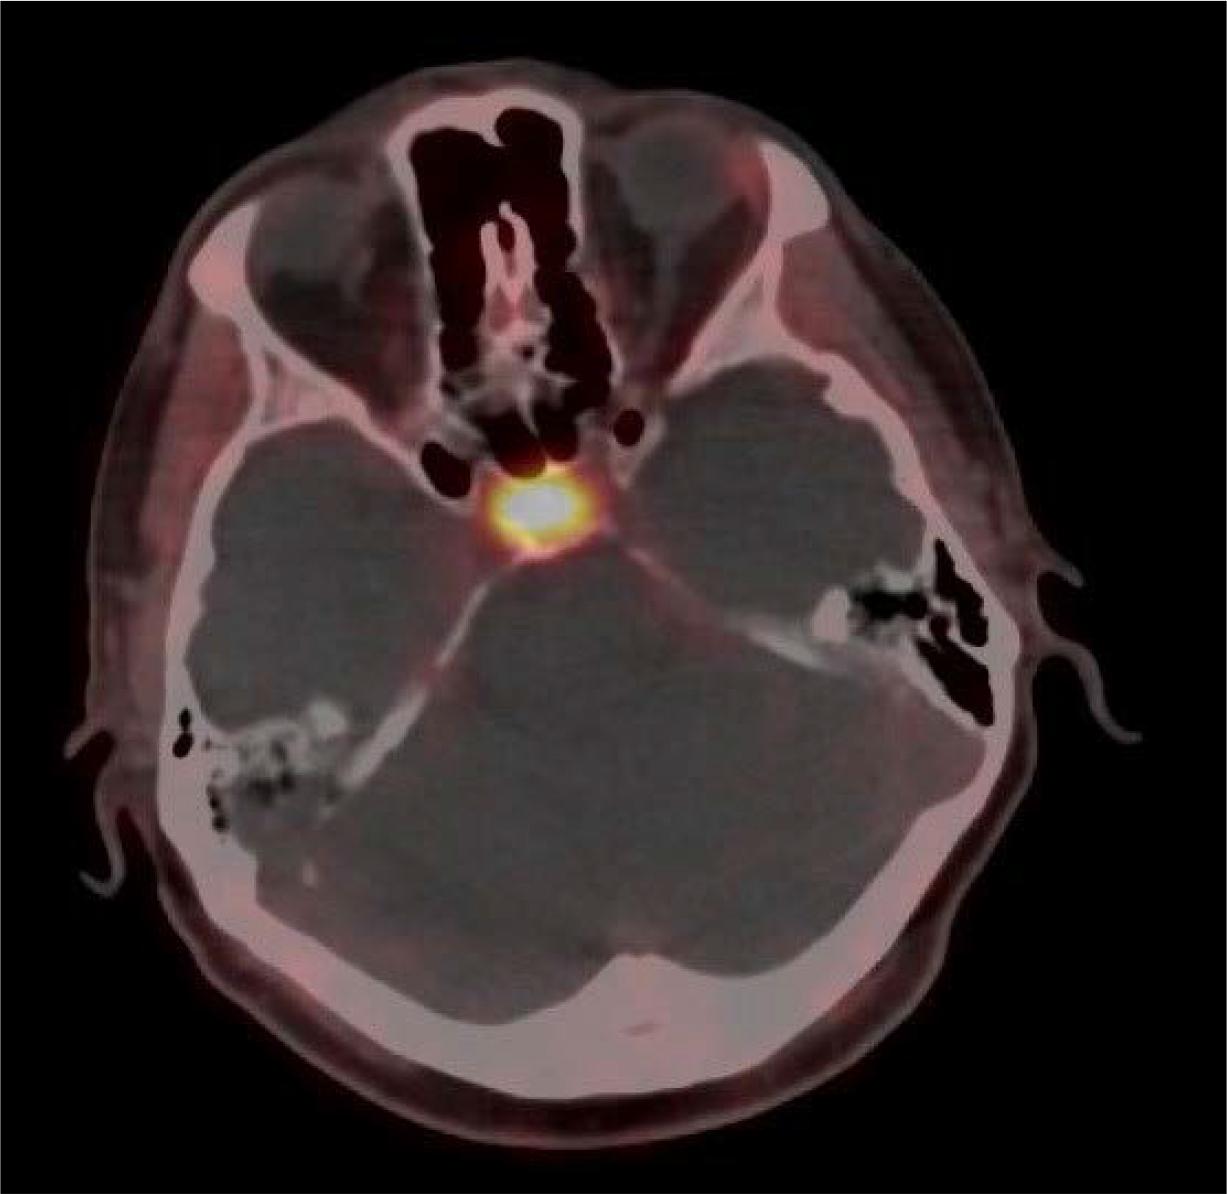

In addition, mild uptake was noted in the pituitary gland, which raised the suspicion of a macroadenoma.

[68Ga]Ga-DOTA-TATE PET/CT, axial plane-increased uptake in the pituitary gland, correlating with MRI findings of a suspected macroadenoma, in line with MEN 1 syndrome.